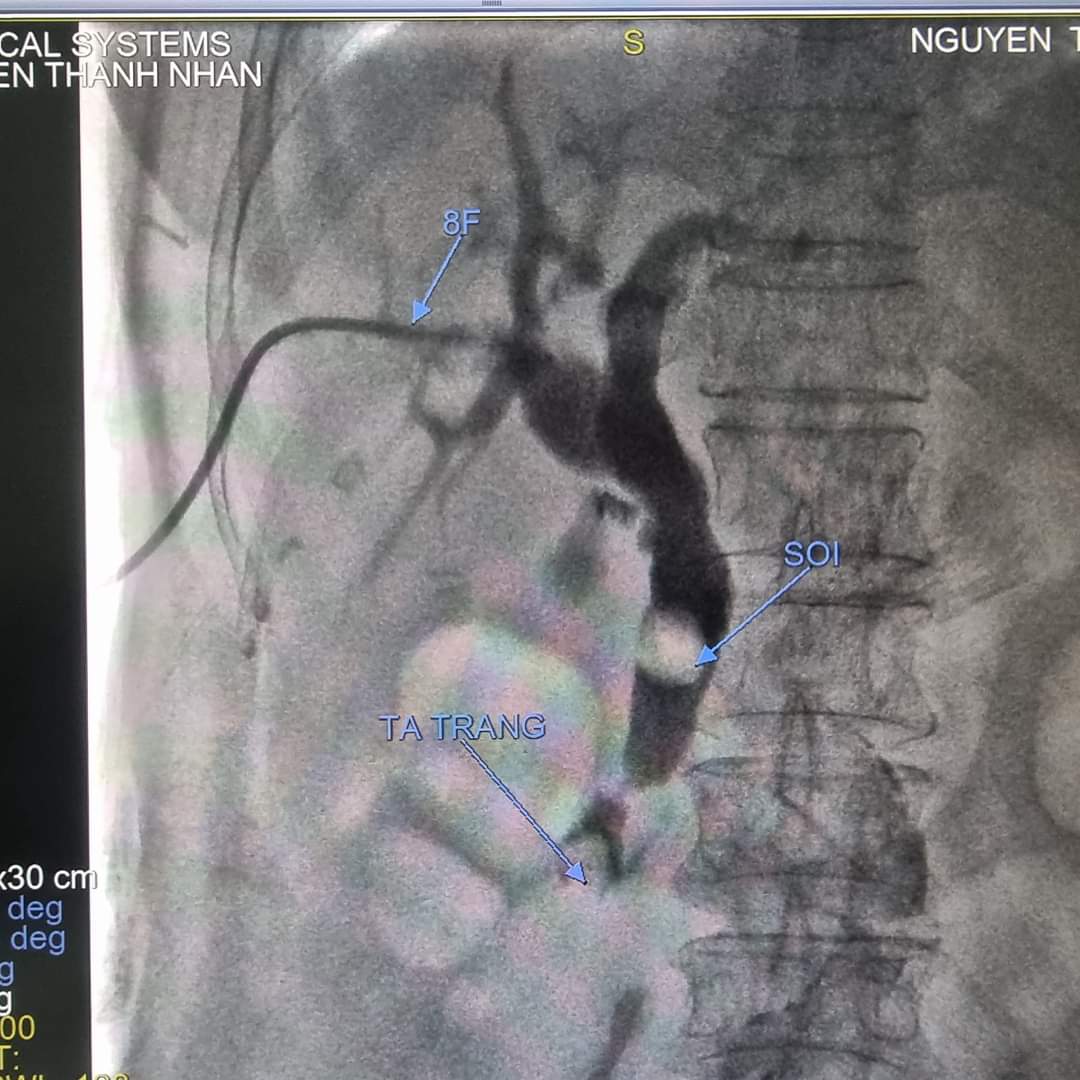

Tháng 1 năm 2023, khoa Ngoại tổng hợp 1 bệnh viện Thanh Nhàn tiếp nhận bệnh nhân nam 63 tuổi vào viện vì sốt cao và đau bụng, bệnh nhân có tiền sử mổ sỏi mật 2 lần. Bệnh nhân được làm bilan chẩn đoán: Tắc mật do sỏi ống mật chủ tái phát

Hình 1: Phim chụp trước mổ